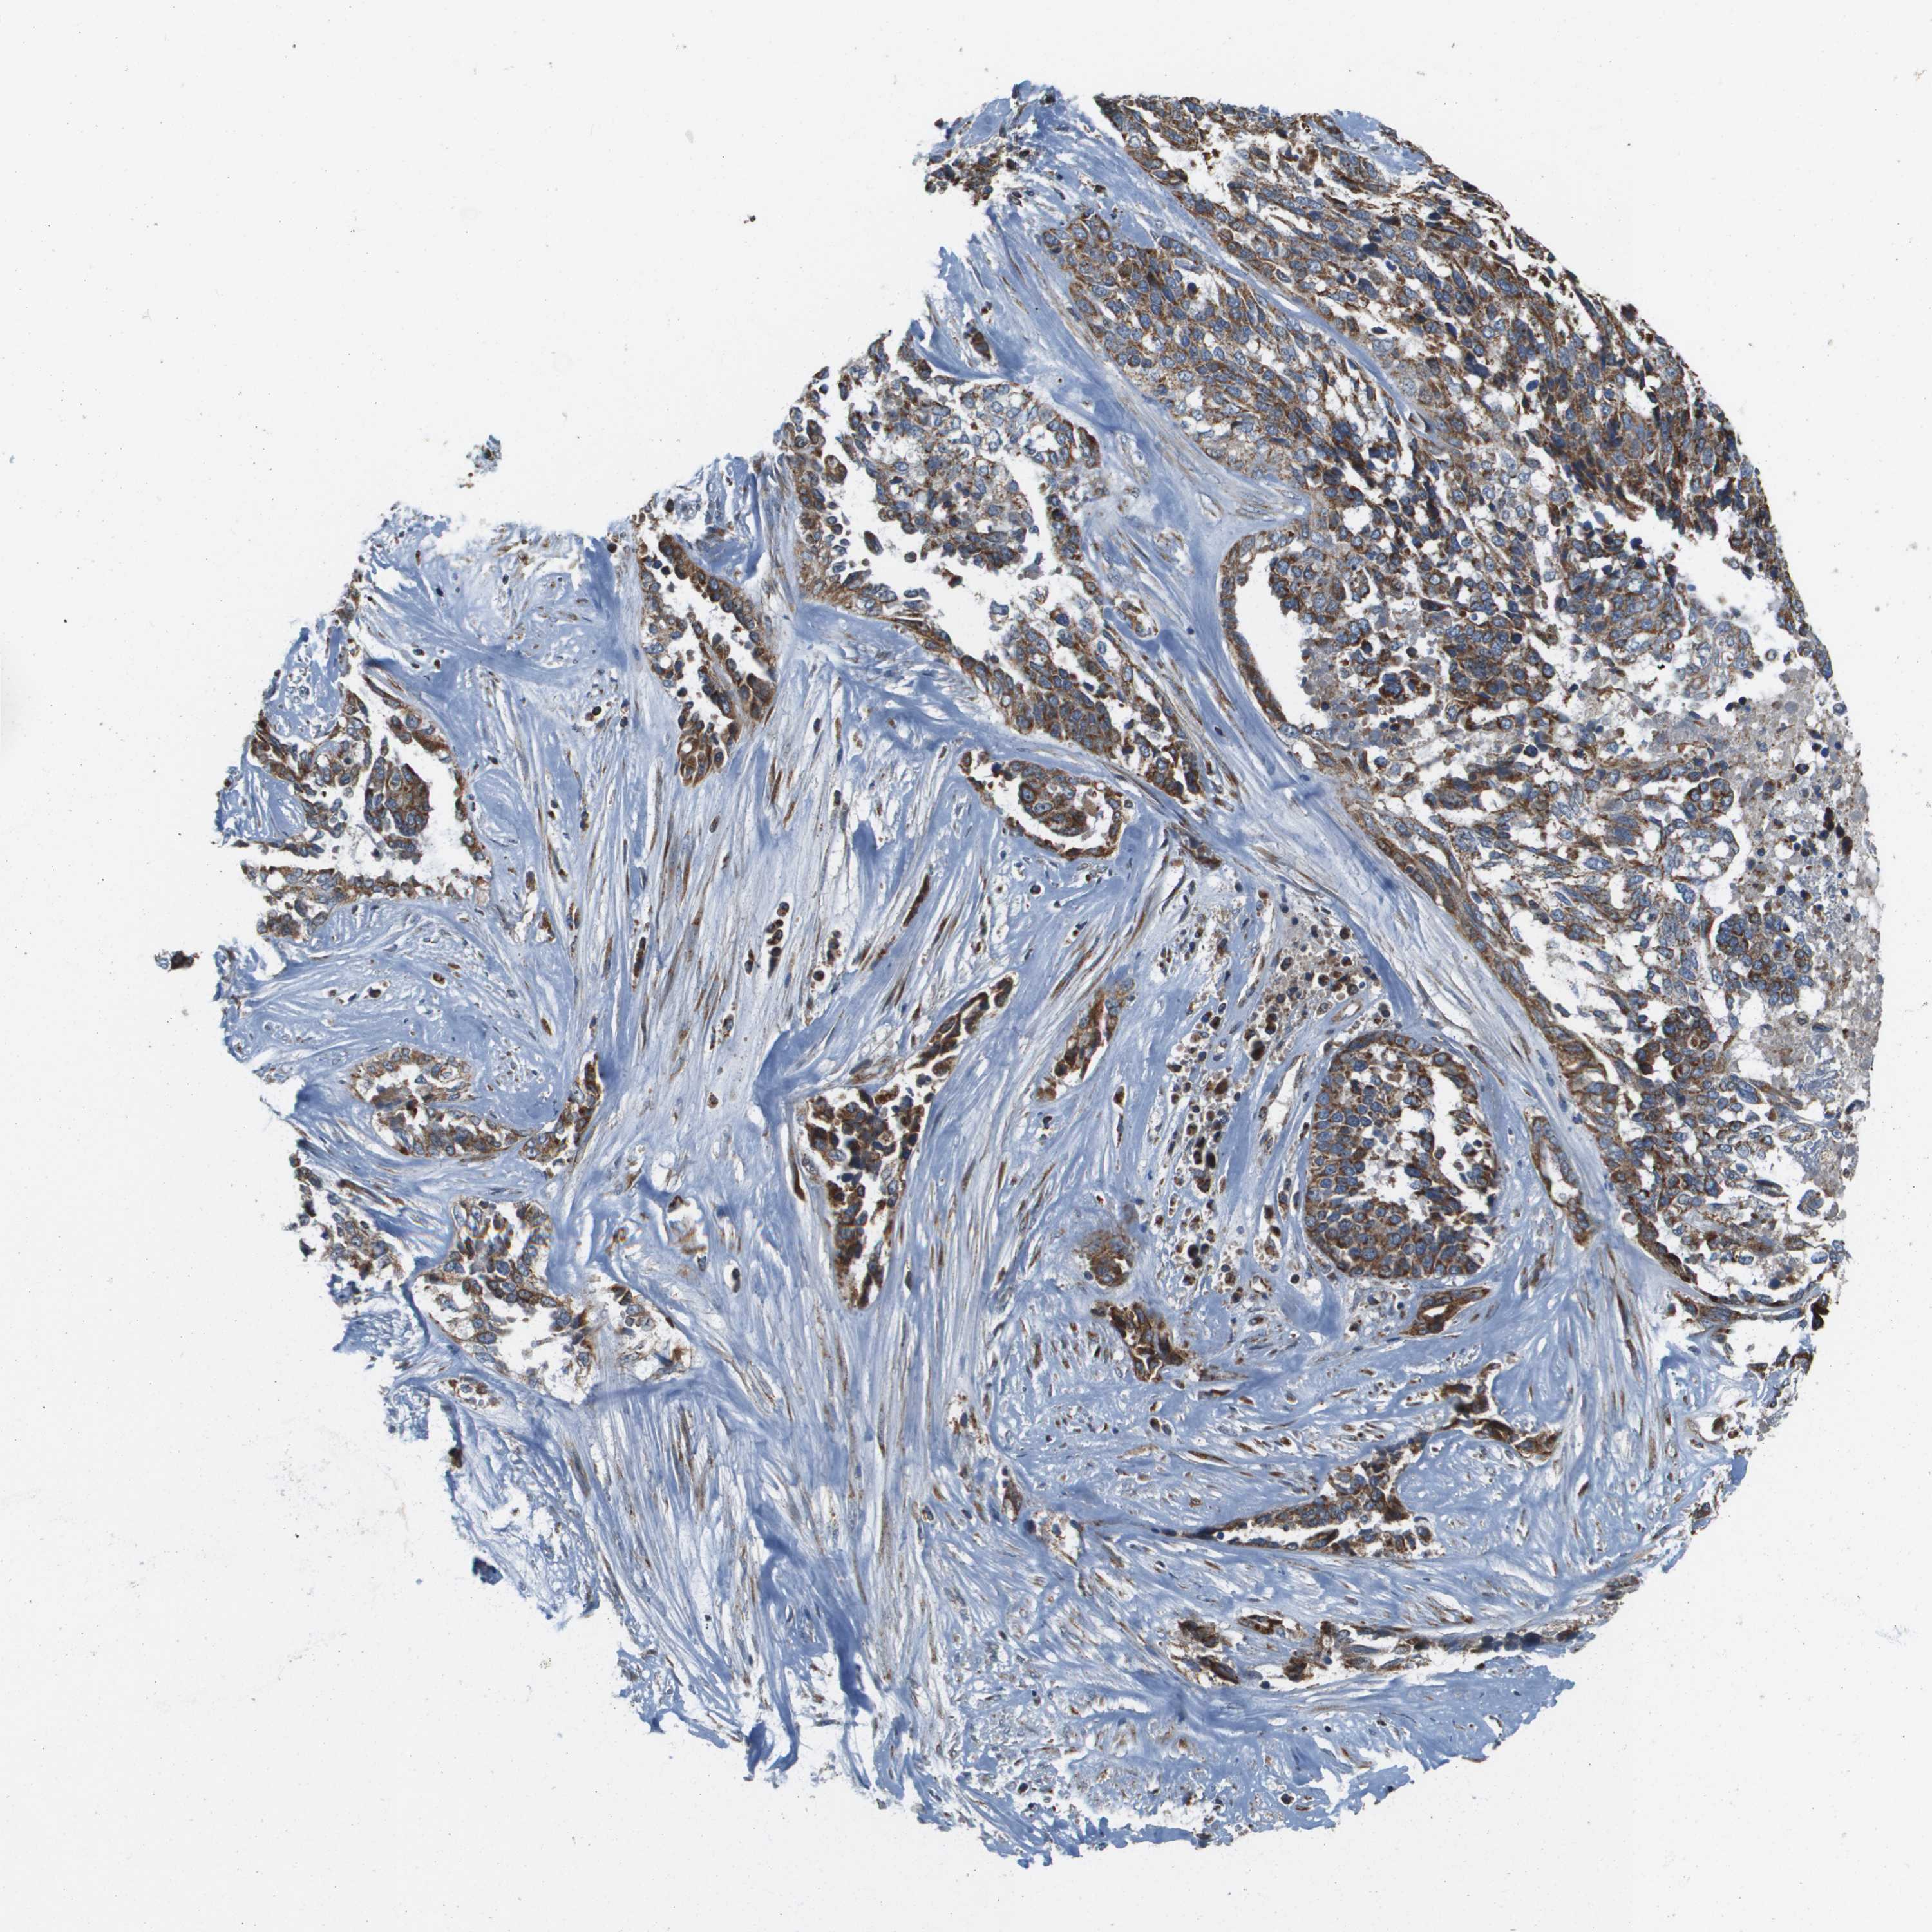

OVARIAN CANCER - Protein expressioni

A mouse-over function shows sample information and annotation data. Click on an image to view it in a full screen mode. Samples can be filtered based on level of antibody staining by selecting one or several of the following categories: high, medium, low and not detected. The assay and annotation is described here.

Note that samples used for immunohistochemistry by the Human Protein Atlas do not correspond to samples in the TCGA dataset.

Antibody stainingi

Antibody staining in the annotated cell types in the current human tissue is reported as not detected, low, medium, or high, based on conventional immunohistochemistry profiling in selected tissues. This score is based on the combination of the staining intensity and fraction of stained cells.

Each image is clickable and will lead to virtual microscopy that enables deeper exploration of all samples and also displays staining intensity scores, fraction scores and subcellular localization as well as patient and tissue information for each sample.

Antibody HPA017238

Staining

High

Medium

Low

Not detected

Intensity

Strong

Moderate

Weak

Negative

Quantity

>75%

75%-25%

<25%

None

Location

Nuclear

Cytoplasmic/membranous

Cytoplasmic/membranous,nuclear

Cystadenocarcinoma, serous, NOS

Carcinoma, endometroid

Cystadenocarcinoma, mucinous, NOS

Carcinoma, NOS